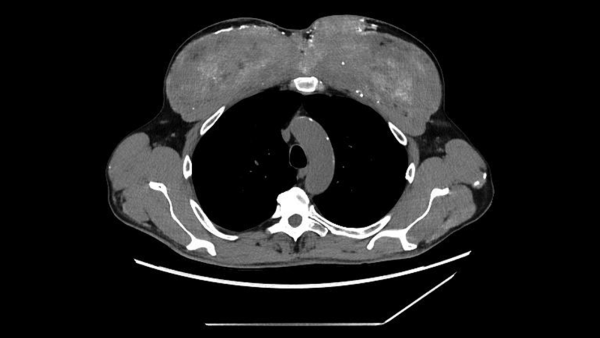

The diagnosis: Afterward, the medical staff examined the patient’s soft tissue via CT scanning. From these scans, they spotted a deposit of trapped nitrogen gas within the patient’s abdominal area, just above his stomach and beneath his lungs — a state known as pneumoperitoneum. This verified that the gas had ruptured the man’s stomach and gathered on top of it.